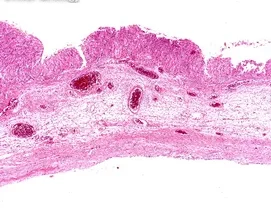

- Seroza Kistler: Yumurtalıkta sıvı dolu ve genellikle iyi huylu olan kistlerdir.